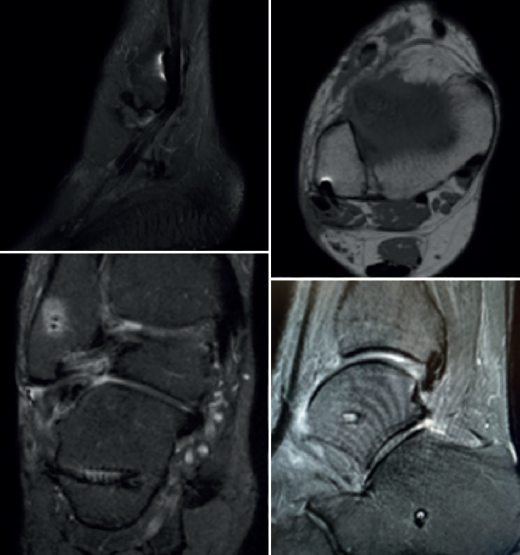

Bajo la sospecha de un fracaso de la reconstrucción ligamentosa, se realizó una resonancia magnética que reveló acumulación de líquido alrededor de la vaina de los peroneos y un engrosamiento leve del tendón peroneus longus a nivel inframaleolar, sin evidencia clara de rotura del tendón; sin embargo, la presencia de material metálico dificultaba su interpretación (Figura 2).

Figura 2. Cortes en secuencias T1 y T2 de resonancia magnética mostrando el dispositivo cortical correctamente situado en la cortical posterior del peroné y los túneles normoposicionados. Acumulación de líquido en la vaina del peroneo.